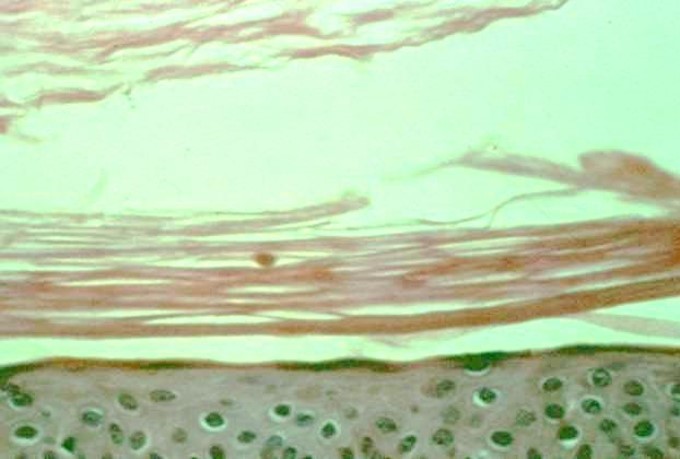

What disease process is pictured below?

Lentigo